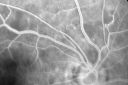

PHOTOGRAPHS: Photos confirm clinical findings.

FLUORESCEIN ANGIOGRAPHY: FA shows some telangiectasis of the retinal capillaries. There is no evidence of any retinal vascular occlusions.

AIDS - HIV Retinopathy - Cotton Wool Spots981 views54-year-old woman HIV positive for 18 years. Her CD4 count is currently less than 50 and she was hospitalized for pneumocystis carinii pneumonia 5 months ago. She has noticed just for the last few weeks a few blind spots in the paracentral vision. Predominantly out of her right eye when she closes her left eye, she sees a few temporal blind spots. VA 20/25 in both eyes.      (0 votes)